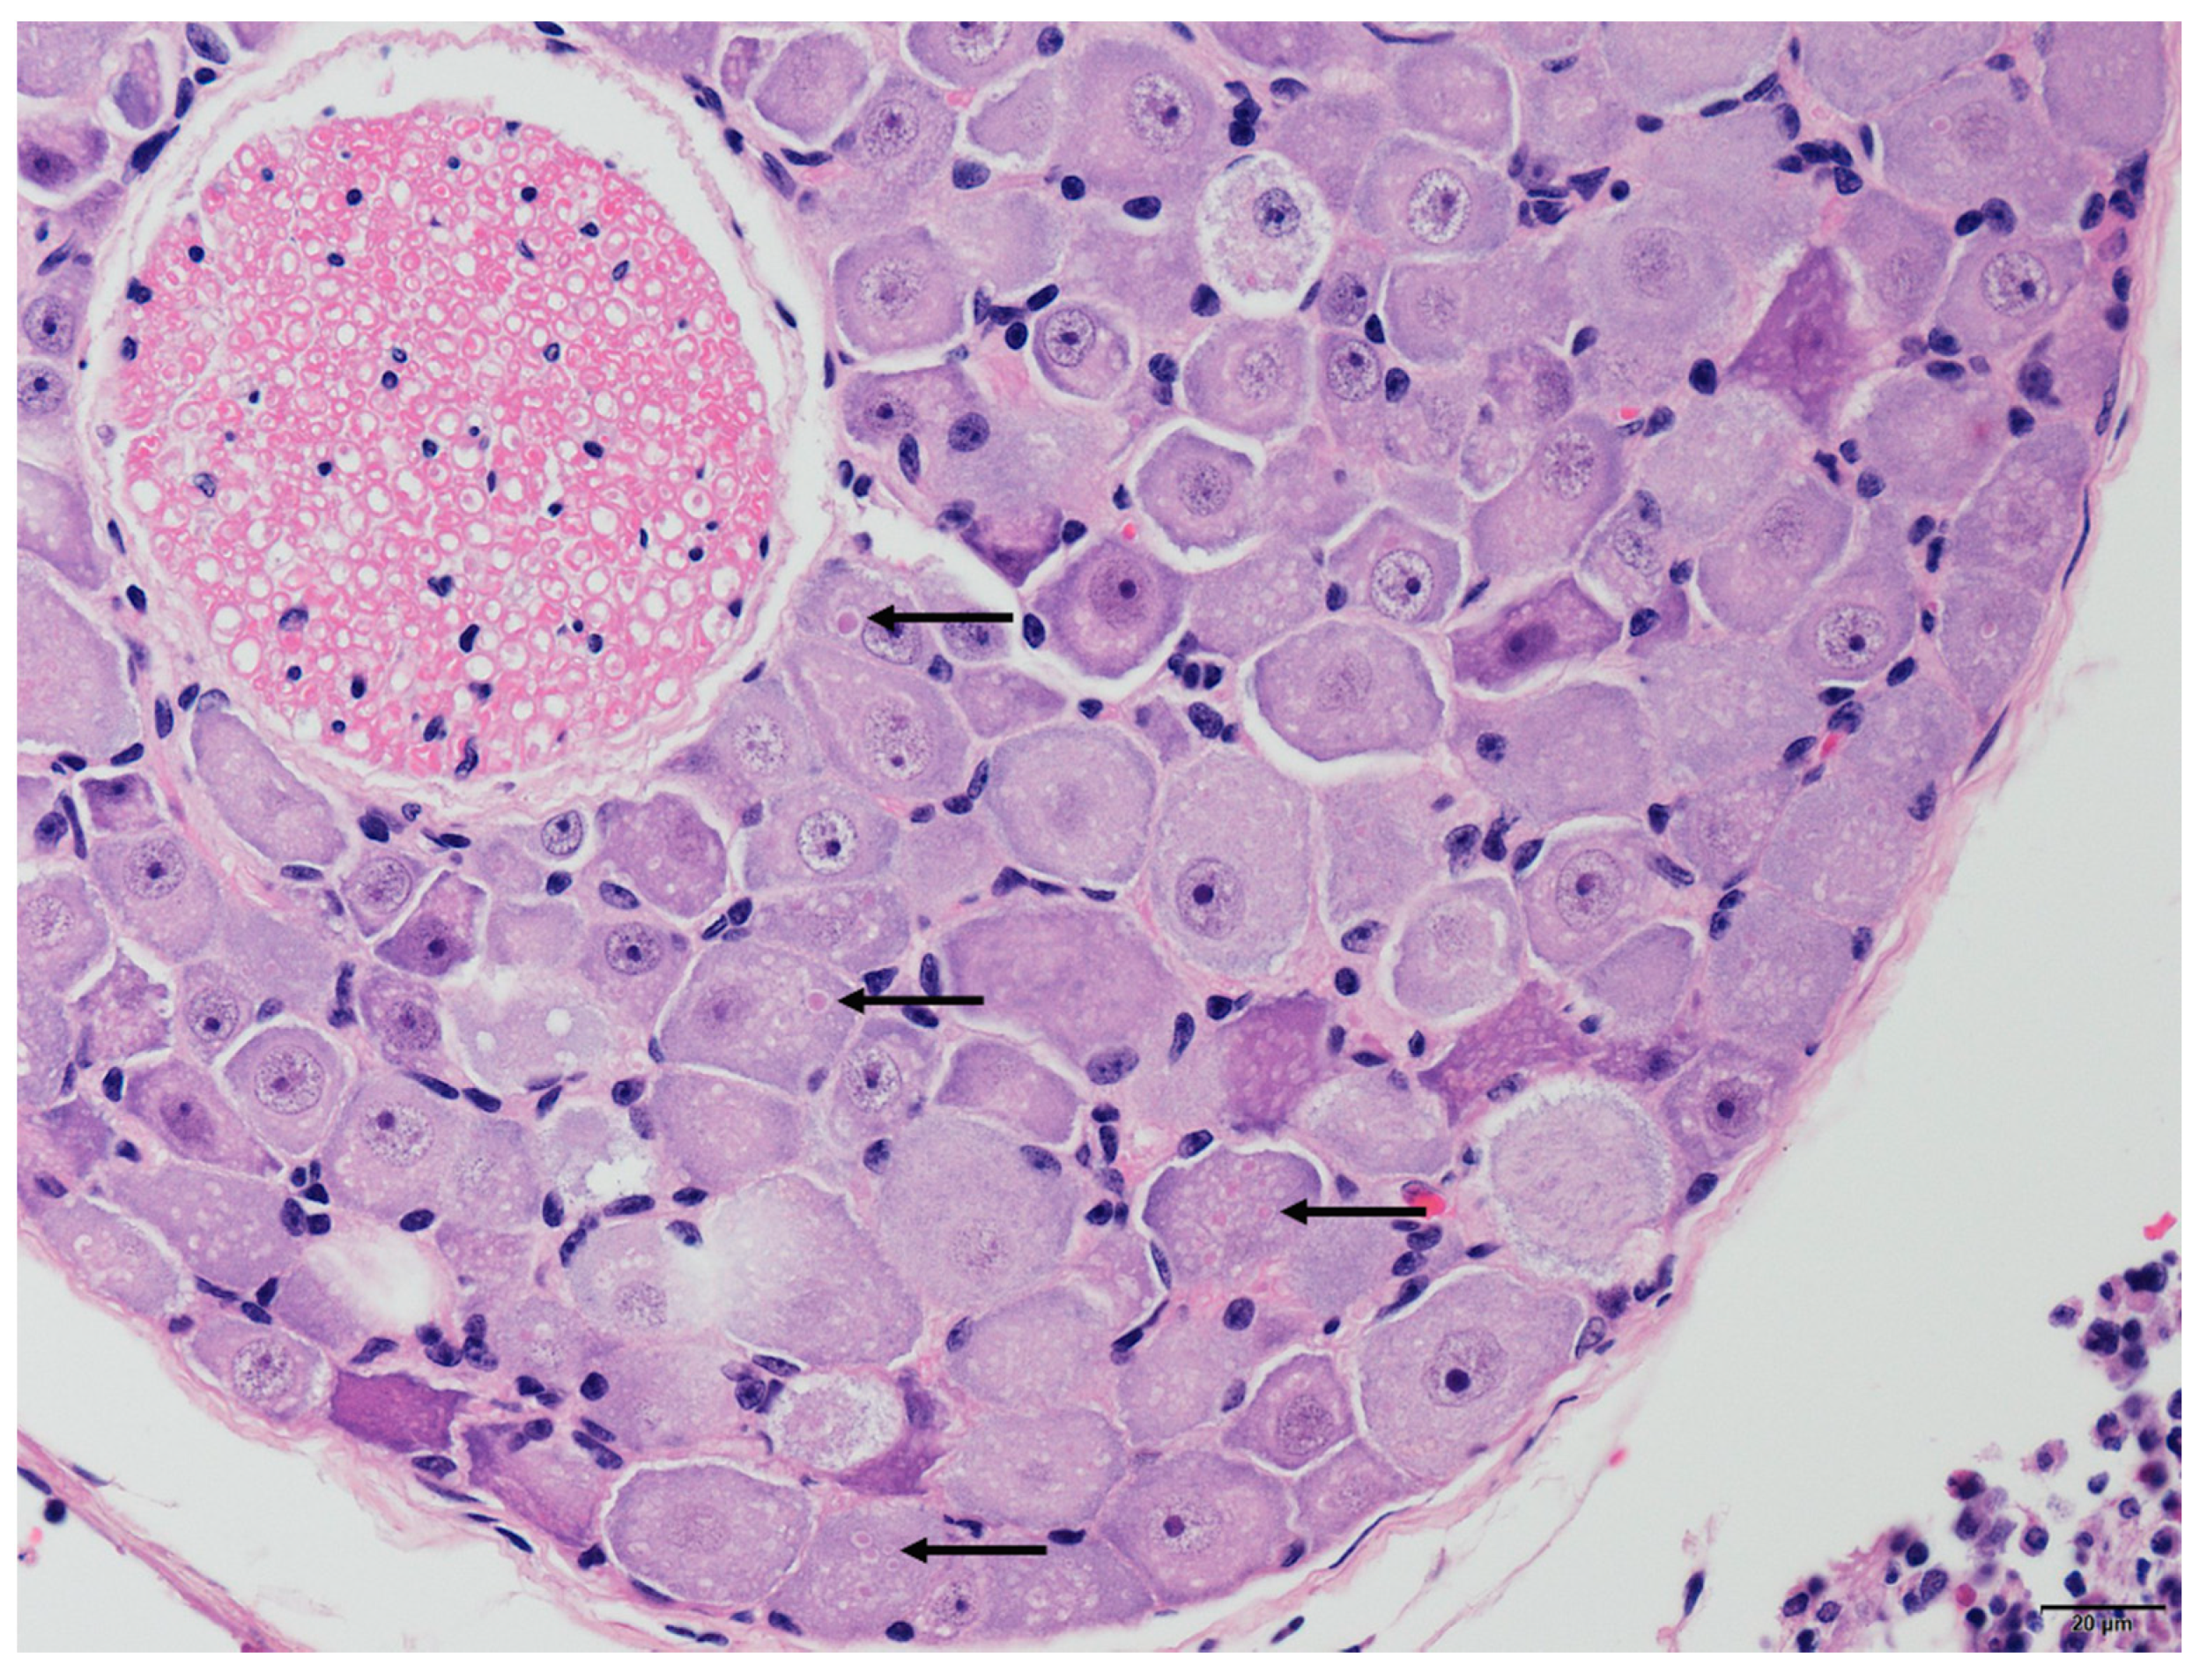

3.3. Histopathological Examination